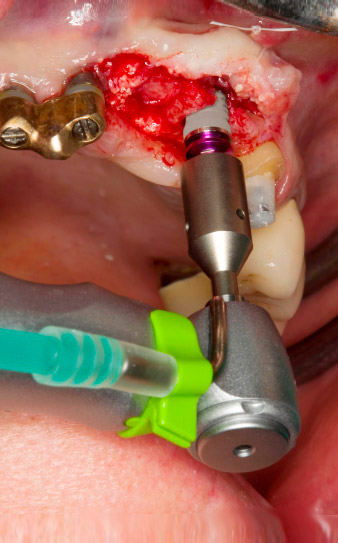

Enroscado mecánico del implante con el contra-ángulo WS-75 L

Imagen 4: Enroscado mecánico del implante con el contra-ángulo WS-75 L con una transmisión de 20:1 (programa P5).